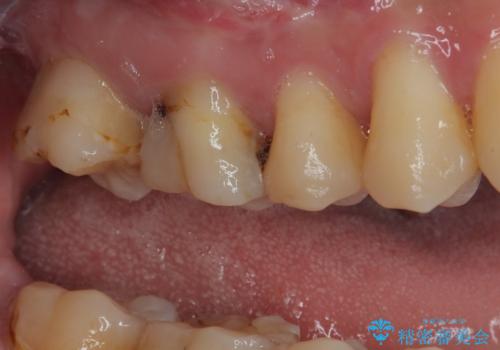

- 他院で矯正治療前後に処置を行った歯が痛むとのことで来院された患者様です。

下顎大臼歯は根管治療がされている歯が咬合時に痛みを感じ、上顎の大臼歯2歯は冷たいものがしみる状態でした。

まずはしみる上顎の歯を仮歯に置き換え、その後下顎の根管治療を行った上で、異常が認められなければオールセラミッククラウンにて補綴治療を行うこととしました。

上顎は仮歯に置き換えた後に、それまでの痛みは一切感じなくなり、下顎も一度目の根管治療で痛みを感じることはなくなりました。